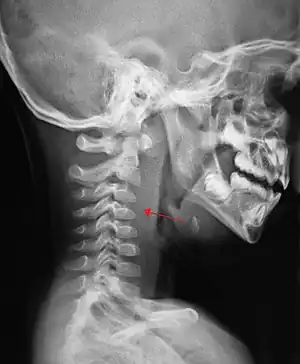

If more than half of the size of the C2 vertebra, it may indicate retropharyngeal abscess.[7]